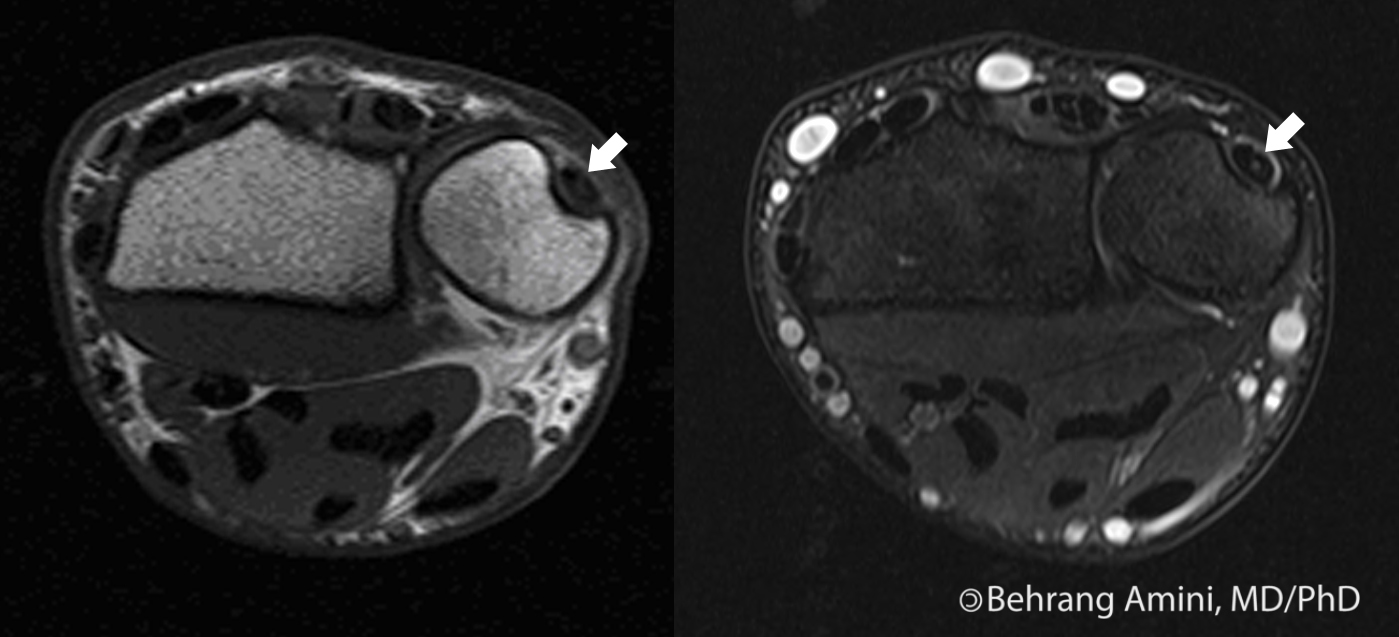

Extensor Carpi Ulnaris MRI

Extensor Carpi Ulnaris Subluxation — Mri Anatomy Extensor Carpi Ulnaris To better understand the anatomy of the forearm extensors, take a look at the following study unit: 3, extensor carpi ulnaris t. Ultrasound and mri are the mainstays of ecu tendon imaging, with ultrasound offering the advantage of dynamic assessment,. The anatomy of ecu results in a relatively. Tendon and its retaining sheath are commonly injured in sport. Ultrasound and. Mri Anatomy Extensor Carpi Ulnaris.

Extensor Carpi Ulnaris MRI Mri Anatomy Extensor Carpi Ulnaris 3, extensor carpi ulnaris t. Tendon and its retaining sheath are commonly injured in sport. The anatomy of ecu results in a relatively. To better understand the anatomy of the forearm extensors, take a look at the following study unit: Ultrasound and mri are the mainstays of ecu tendon imaging, with ultrasound offering the advantage of dynamic assessment, doppler interrogation. Mri Anatomy Extensor Carpi Ulnaris.